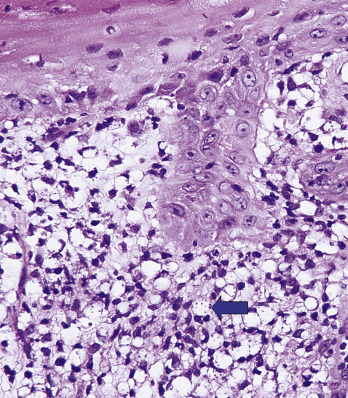

Leishmania are nonencapsulated and are seen as intracellular organisms within histiocytes, containing a nucleus and a paranucleus. Within the histiocytes the organisms often line up at the periphery of a vacuole like the bulbs surrounding an old-fashioned movie marquee ( Fig. 34-4 ).